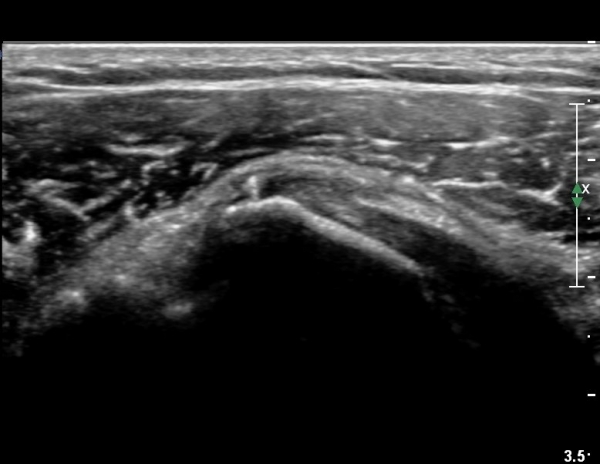

°ß°©ÇϱٰǠ Á¾´Ü¸é°Ë»ç¿¡¼­ °ÇºÎÂøºÎ¿¡ ÀÛÀº ¼®È¸È­À½¿µÀÌ °üÂûµÊ(»çÁø 2).